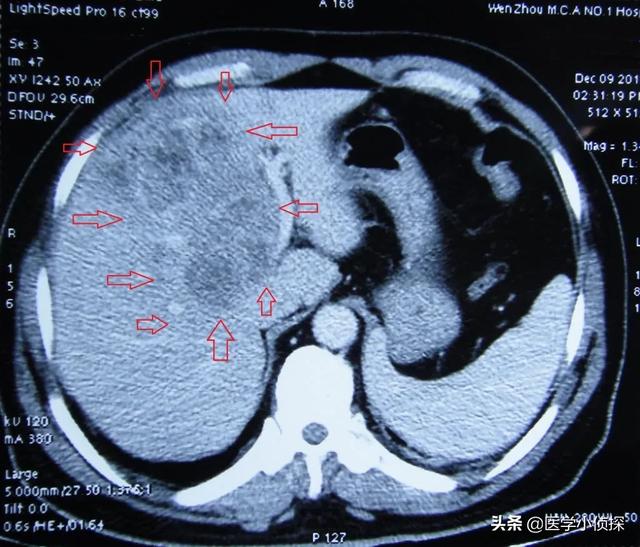

- Si une échographie du foie ne révèle pas de tumeur dans le foie, ou si la nature de la tumeur ne peut être déterminée, une alpha-fœtoprotéine élevée est hautement suspecte de la présence possible d'un carcinome hépatocellulaire.Une tomodensitométrie du foie peut être réalisée.Je recommanderais d'emblée une tomodensitométrie améliorée du foie, car cette technique est relativement efficace pour identifier les tumeurs hépatiques.

(Comme indiqué : cancer du foie métastatique)

Ce cancer du foie métastatique est encore relativement fréquent en clinique, car le foie est le plus grand organe digestif de notre corps.La circulation sanguine y est très richePresque tout le sang de notre corps, y compris le sang provenant du tractus gastro-intestinal, est filtré par le foie, et un grand nombre de nos nutriments y sont métabolisés.,De nombreux cancers locaux sont donc sujets à des métastases hépatiques et forment un cancer du foie métastatique.